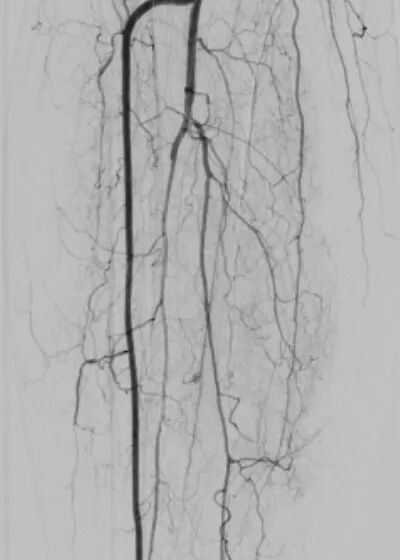

另一个病例中,患者病情更为复杂。术前CTA检查显示,其股浅动脉至腘动脉全程闭塞,血管外科将这种情形称为“长段无光区”。传统治疗中,开通此类如同“水泥管”般的长段闭塞血管,难度极大,术者如同在黑暗中摸索,导丝极易误入内膜下形成夹层,导致手术失败。

2.png

术中,血管外科团队以IVUS为“导航”,在其实时监视下,导丝精准找到血管真腔入口,顺利通过全程闭塞段,成功避免夹层发生,顺利打通患者腿部“生命通道”。针对血管开通后管腔内的严重增生性病变,团队采用准分子激光消融术进行减容处理,通过激光导管冷光源精准气化斑块,进一步恢复了血管正常内径。